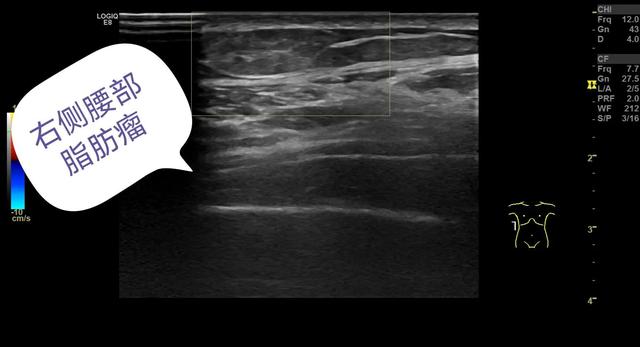

经常有患者因为胳膊、大腿、腰背部、颈肩部等摸着有肿块来医院检查,一般接诊这样的患者我们都会问,“发现多长时间了”,患者回答“好多年了,以前小,最近感觉长大了或者是没注意,偶然发现的”,继续问“别的地方还有吗”,回答“有,好多地方都有”,这种肿块摸起来很柔软、活动度比较好,超声检查下可见皮下脂肪层内低回声、等回声或者高回声结节,形态一般都比较规则,呈圆形或椭圆形,边界一般比较清晰,结节内部可见条索样高回声,结节内部一般无血流信号,探头加压结节可发生形变。超声诊断:脂肪瘤可能。

作为一名超声医生,其实更关注的是脂肪瘤的超声表现,它在超声上可以表现为低回声结节、等回声结节或者是高回声结节,形态一般呈椭圆形或者分叶状,边界清,结节内部一般无明显血流信号,不过这也要取决于脂肪瘤内部有无其他成分,如含有血管成分多,可伴有少量血流信号。

下面给大家分享几个我平时做的病例,发生在各个部位的脂肪瘤。

等回声的脂肪瘤,无血流信号